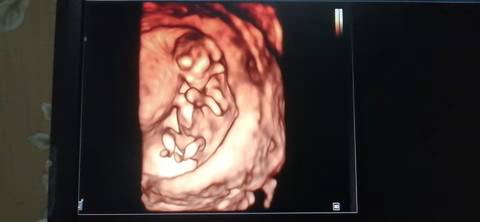

十二周的nt,是不是小棉袄啊? 医生给看宝宝腿的时候生殖器那里是平平的,是女宝吗?我和老公都挺想要小棉袄的

你好,我们是看不出来的,只要是健康的宝宝,都是上帝赐予的礼物,孕期定期检查,祝心想事成 。

亲,这个上面来看确实判断不了的,顺其自然就好了,别给自己太大压力,心想事成。